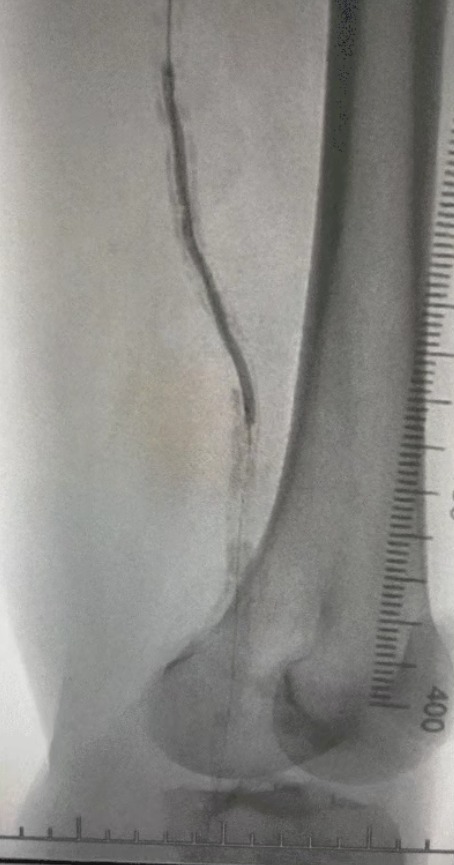

· Badanie fizykalne: słabe pulsy udowe; brak pulsów podkolanowych i grzbietu pedis; owrzodzenie lewego pierwszego palca; martwica prawego pierwszego i drugiego palca

· Obrazowanie przedoperacyjne: Ciężkie, rozproszone zwapniałe zwężenie w obustronnych tętnicach kończyn dolnych

Biorąc pod uwagę złożony stan naczyniowy, wybraliśmy system cewnika dylatacji balonowej ThorCrack Peripheral IVL. Ze względu na ograniczoną tolerancję pacjenta wykonano etapowe zabiegi interwencyjne na obu kończynach dolnych.

Wynik chirurgiczny

Po zabiegu znacznie poprawiło się zwężenie tętnic, zwiększył się przepływ krwi i wzrosła temperatura skóry. Nie wystąpiły powikłania pooperacyjne. Zarówno pacjent, jak i zespół chirurgiczny byli bardzo zadowoleni z wyników.